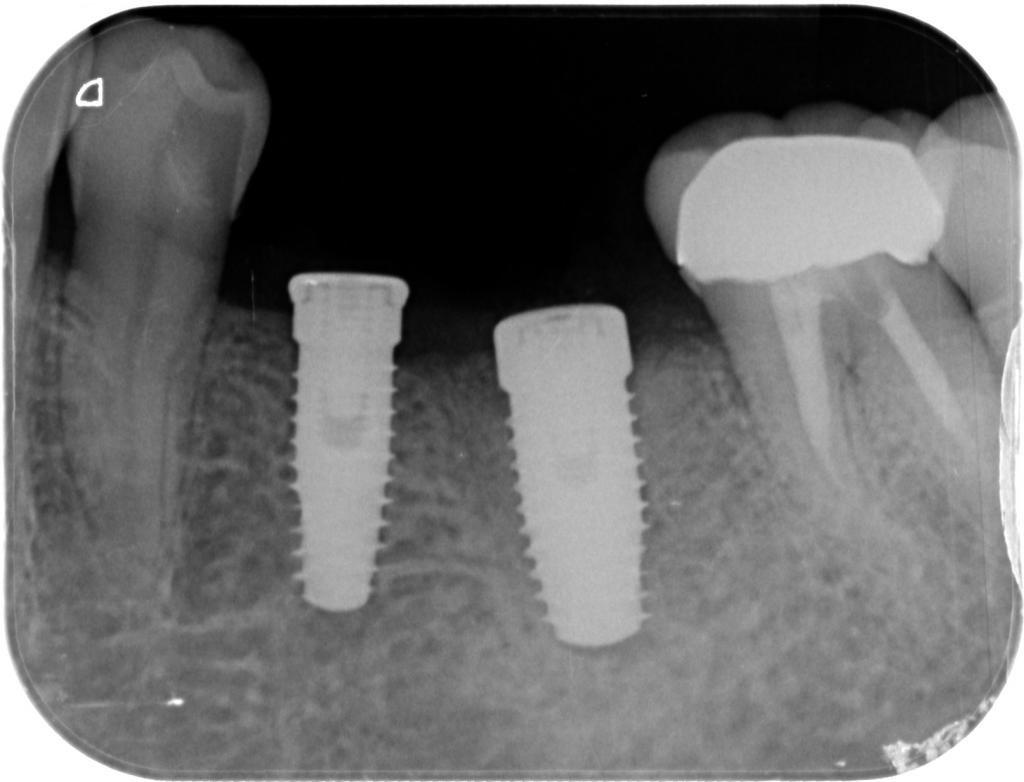

- 埋入直後のレントゲン写真です。

適切な位置に2本、埋入されています。